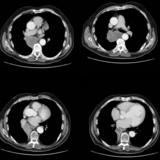

Mass  RLL collapse 5 CT

Date: 03/02/2006

Views: 3886